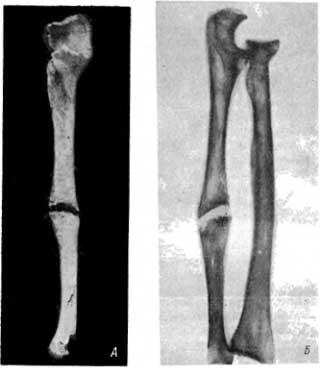

При раскопках в том же городище был обнаружен скелет женщины (возраст около 45 лет). В средней трети диафиза правой локтевой кости имелся перелом с исходом в ложный сустав (рис. 15, А и Б). Наступающие в этих случаях изменения на мацерированных костях редко описывались. В этом новообразованном суставе дистальный отломок кости играл роль головки; возникшая в области повреждения замыкающая пластинка была очень тонкой (как в нормальных головках). Поврежденная же поверхность проксимального отломка служила суставной впадиной. Возникшая на ней замыкающая пластинка была склерозированной (как в нормальных суставных впадинах). Необычные условия движения и нагрузка привели к преждевременному деформирующему артрозу в локтевом суставе. Кости правого предплечья в общем тоньше (атрофичнее) костей левого предплечья.

Рис. 15. А — ложный сустав в локтевой кости, возникший после перелома Б — рентгенограмма локтевой кости с ложным суставом и нормальной лучевой кости.

Следует отметить, что до нас ложный сустав на обеих костях правого предплечья описал К. 3. Яцута на скелете, добытом С. А. Локтюшевым из кургана вблизи Славяносербска (захоронение II в. до н. э.). Изучение костей правого предплечья показало наличие движений в новообразованном суставе. Однако кости левого предплечья отличались большей мощностью, ибо основная нагрузка падала на левую верхнюю конечность, правую же этот человек щадил.[65]